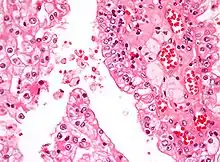

| Micrograph showing the most common type of kidney cancer (clear cell renal cell carcinoma). H&E stain. | |

The most common type of kidney malignancy is renal cell carcinoma,[33] which is thought to originate from cells in the proximal convoluted tubule of the nephron.[15][34] Another type of kidney cancer although less common, is transitional cell cancer (TCC) or urothelial carcinoma of the renal pelvis.[35] The renal pelvis is the part of the kidney that collects urine and drains it into a tube called the ureter.[35] The cells that line the renal pelvis are called transitional cells, and are also sometimes called urothelial cells. The transitional/urothelial cells in the renal pelvis are the same type of cells that line the ureter and bladder. For this reason TCC of the renal pelvis is distinct from RCC and is thought to behave more like bladder cancer.[35] Other rare types of kidney cancers that can arise from the urothelial cells of the renal pelvis are squamous cell carcinoma and adenocarcinoma.[15]

Renal cell carcinoma has been further divided into sub-types based on histological features and genetic abnormalities. The 2004 WHO Classification of the Renal Tumors of the Adults describes these categories:[39]

- Clear cell RCC